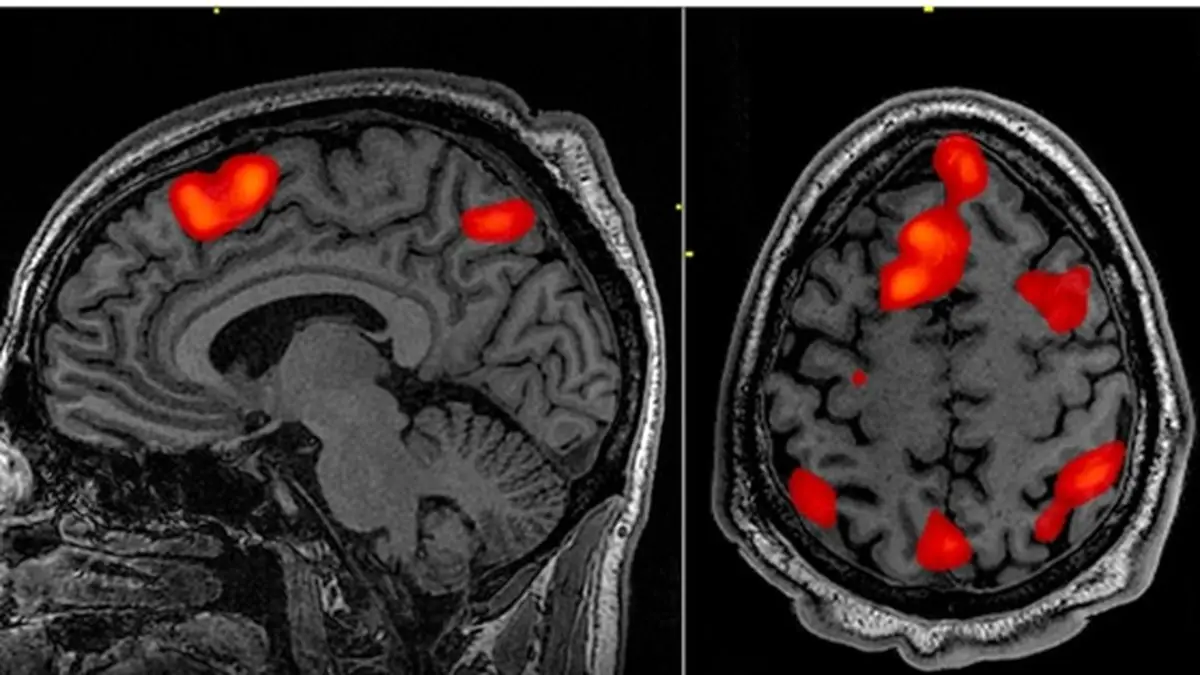

به گزارش رکنا، امروزه تصویربرداری مغزی به‌عنوان یکی از ابزارهای مهم و پیشرفته در علوم اعصاب شناختی و روان‌شناسی شناخته می‌شود. این حوزه با بهره‌گیری از تکنولوژی‌های نوین، ابزارهای متنوعی برای بررسی عملکرد مغز انسان در اختیار ما قرار داده است. یکی از تازه‌ترین فناوری‌ها در این عرصه، طیف‌نگاری کارکردی مادون قرمز نزدیک (fNIRS) محسوب می‌شود؛ روشی که به دلیل غیرتهاجمی بودن و سهولت در استفاده، به سرعت مورد توجه پژوهشگران قرار گرفته است.

با کمک این فناوری، تغییرات در میزان اکسیژن‌رسانی خون به نواحی مختلف قشر مغز اندازه‌گیری می‌شود و اطلاعات مهمی در خصوص فعالیت‌های شناختی و رفتاری انسان به دست می‌آید. این روش در مقایسه با فناوری‌هایی مانند EEG و fMRI، امکان انجام مطالعات در شرایط طبیعی‌تر را فراهم کرده و به همین دلیل جذابیت زیادی دارد.

این فناوری بر اساس اصول جذب و بازتاب نور مادون قرمز نزدیک کار می‌کند. دستگاه fNIRS با ارسال نور مادون قرمز به سطح پوست سر و سنجش میزان نور بازتاب شده، تغییرات در نسبت هموگلوبین اکسیژنه و هموگلوبین غیر اکسیژنه را ثبت می‌کند. اطلاعات حاصل از این فرآیند، به‌عنوان شاخص‌های کلیدی برای اندازه‌گیری فعالیت مغزی در زمان واقعی مورد استفاده قرار می‌گیرند.